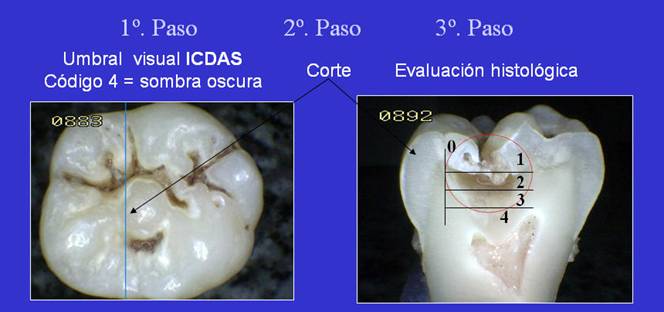

Los

códigos ICDAS fueron ideados

relacionando la puntuación con el grado de gravedad (profundidad

de la caries). Los miembros del grupo ICDAS han demostrado una estrecha

relación entre las puntuaciones y la profundidad histológica. • A modo de ejemplo ver pasos del 1 al 3

en la imagen izquierda.

El sistema de clasificación histológica utilizado se basa

en los criterios de

Ekstrand et al., 1997 que se

enumera abjao:

0 |

No hay

esmalte desmineralizado

o hay una zona estrecha de opacidad |

1 |

Esmalte desmineralizado limitado al

50% de la capa exterior |

2 |

La desmineralización involucra 50% de la capa interior

del esmalte y al tercio exterior de la dentina

|

3 |

La desmineralización involucra al tercio medio de la

dentina |

4 |

La desmineralización involucra al tercio interno de la

dentina |